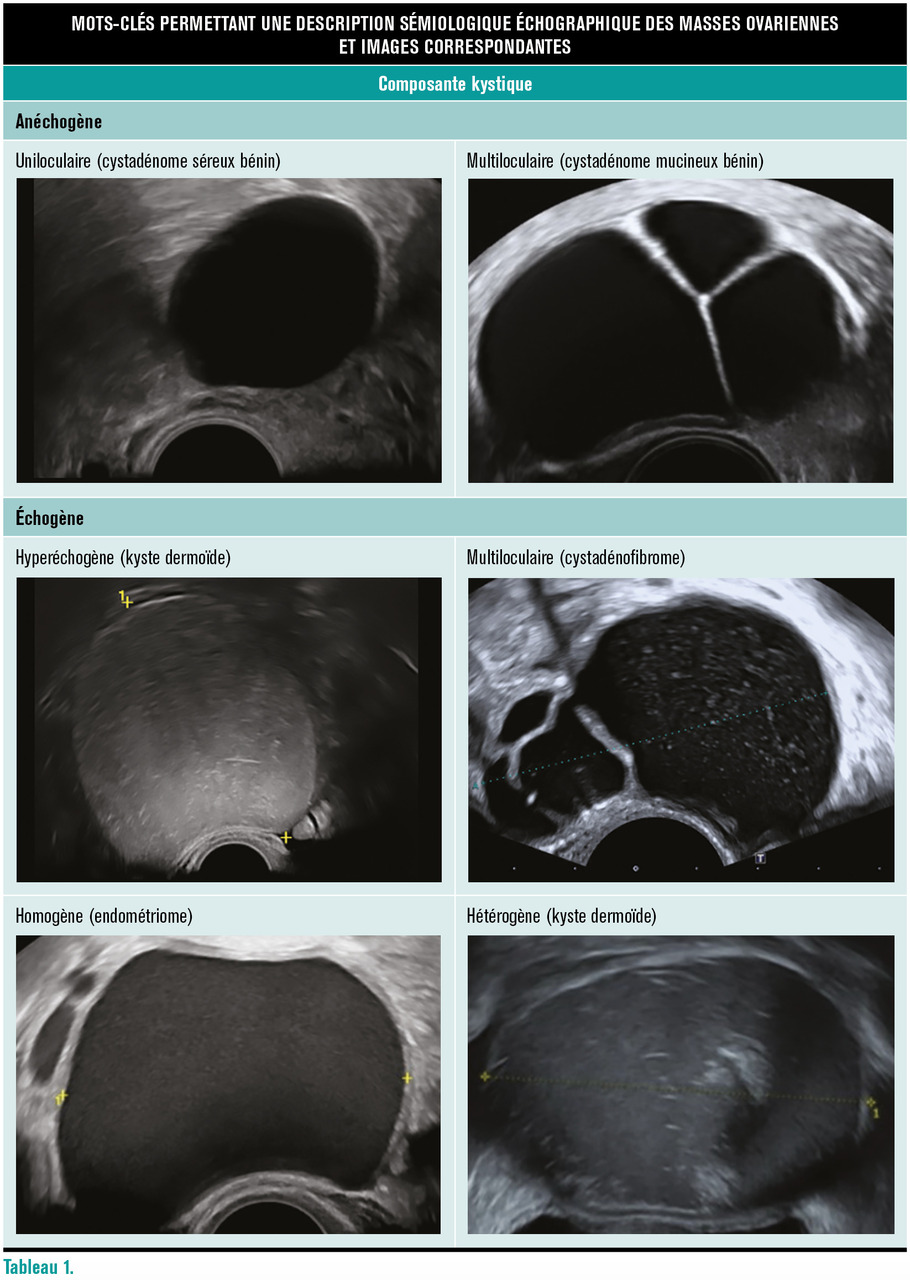

La sémiologie descriptive des masses ovariennes en échographie repose tout d’abord sur l’identification de sa composante majoritaire : kystique pure, à prédominance kystique, à prédominance solide, solide pure.

En cas de portion kystique, il faut décrire sa morphologie (uniloculaire, multiloculaire) et son échogénicité (anéchogène, échogène, homogène ou hétérogène).

Il existe trois types de portions tissulaires : cloison irrégulière, végétations, nodule mural. L’étude de leur vascularisation (absente, faible, modérée, intense) contribue à l’évaluation du risque de malignité de ces lésions (tableau 1).